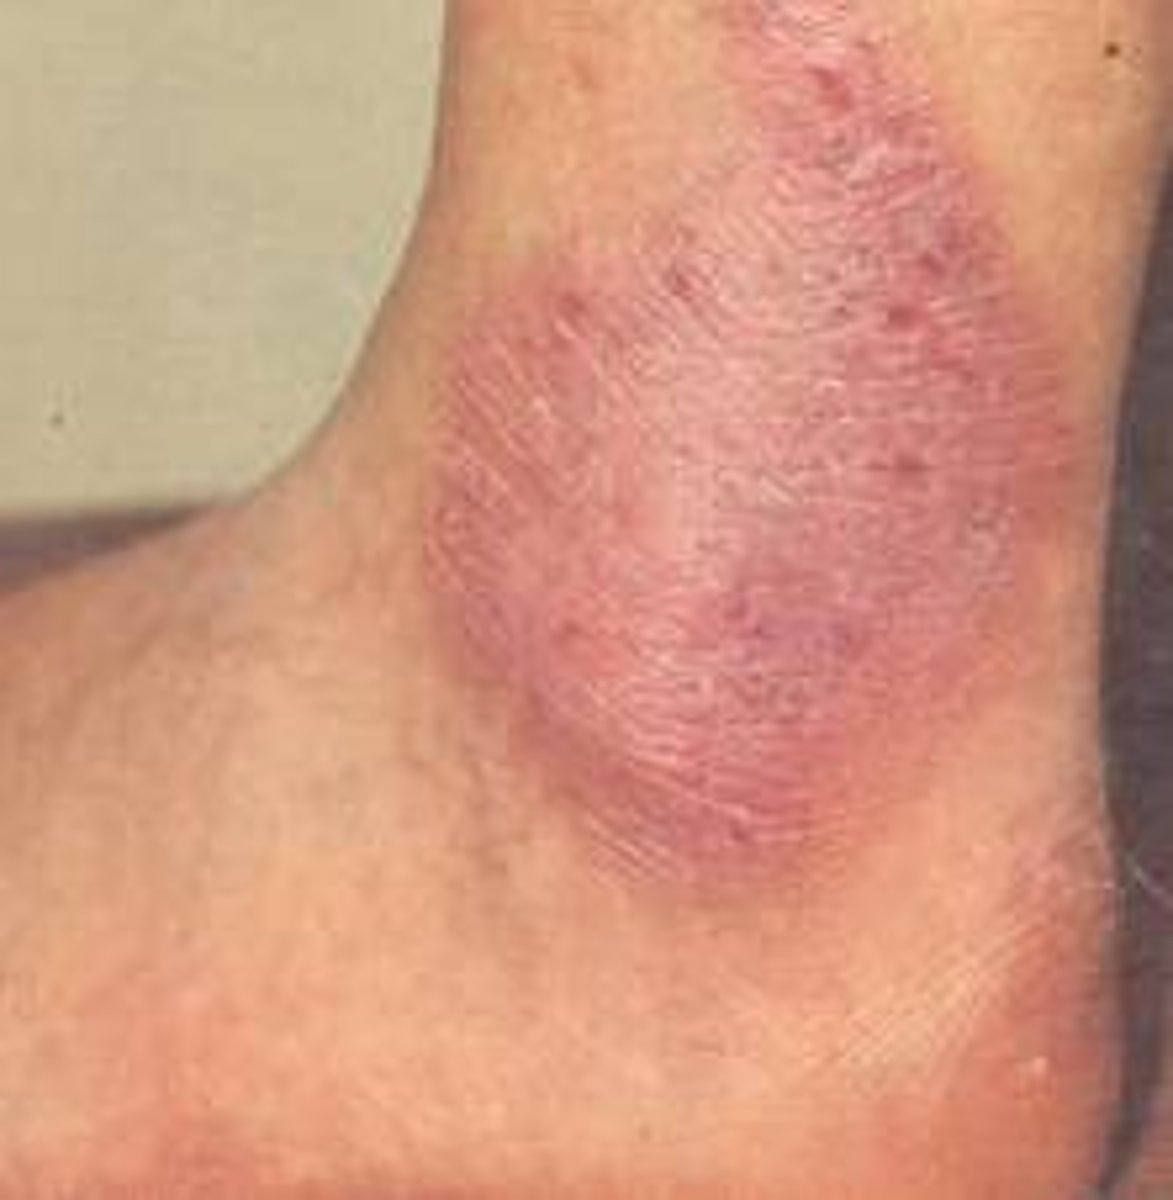

Lichen Simplex Chronicus

diagnose this image

Thick, well- circumscribed plaques that are HIGHLY pruritic (hard to break itch-scratch cycle)